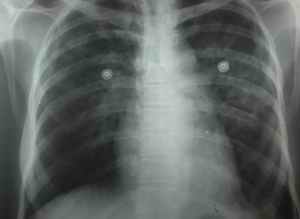

![]() |

A. Initial hypotension is due to loss of fluid such as vomiting, sweating, salivation. Bradycardia is to be treated with intravenous fluid. Hypotension which occurs after 12 hours of sting with warm extremities with tachycardia with or without pulmonary edema responds well to dobutamine drip (5-15 microgram/kg/min). However the recovered victim at the end of 36-48 hours develops asymptomatic hypotension with bradycardia. This is due to the depletion of catecholamine and it is felt that is should be corrected within the next 24 hours.